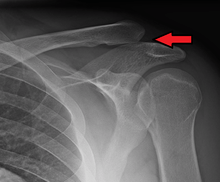

.png) | |

| A Separated Shoulder XRay modified to easily show bones. Notice the separation between the end of the collarbone and the scapula. | |

Diagnosis is based on physical examination and an x-ray. A separated shoulder occurs because of a direct blow to the AC joint or a fall on the elbow that forces the head of the humerus into the AC joint. Furthermore, AC separation can be identified point tenderness, pain at the AC joint with cross-arm adduction, and pain relief with an injection of a local anesthetic. The cross-arm adduction will produce pain specifically at the AC joint and will be done by elevating the arm to a 90° angle, flexing the elbow to a 90° angle, and adducting the arm across the chest. The pain in the shoulder is hard to pinpoint of the innervation of the AC joint and the glenohumeral joint. An injury to the AC joint will result in pain over the AC joint, in the anterolateral neck and in the region in the anterolateral deltoid.